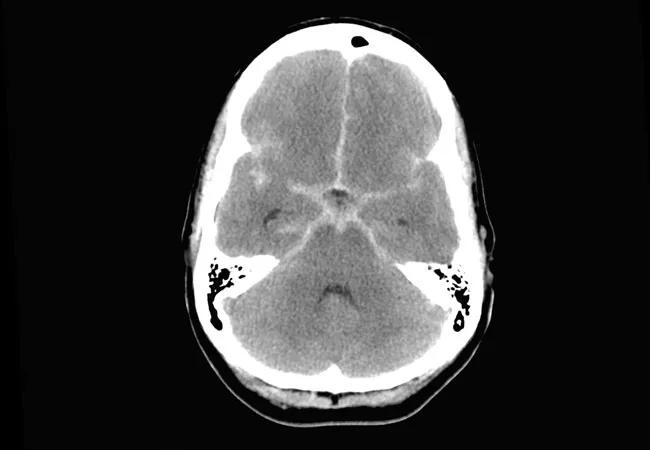

aneurysmal subarachnoid hemorrhage

In the largest reported cohort to be treated with intraventricular milrinone and intravenous (IV) milrinone for cerebral vasospasm (CVS) following an aneurysmal subarachnoid hemorrhage (aSAH), no benefit was found by transcranial Doppler ultrasonography or clinical measures. So reported Cleveland Clinic researchers in a February 20 poster presentation at the 2020 International Stroke Conference.